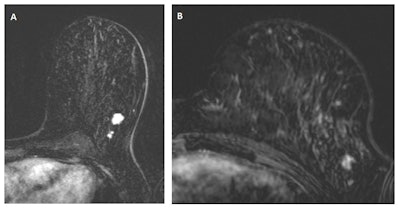

In "A," a multifocal tumor is detected in the left breast of a 49-year-old woman. "B" depicts an MRI scan from the same breast, one year earlier. Despite the lower image quality and the difference in positioning (different scanner and coil), the cancer is clearly visible and should have been recalled according to the consensus read by the radiologists. Images courtesy of Drs. Suzan Vreemann and Ritse Mann.

In "A," a multifocal tumor is detected in the left breast of a 49-year-old woman. "B" depicts an MRI scan from the same breast, one year earlier. Despite the lower image quality and the difference in positioning (different scanner and coil), the cancer is clearly visible and should have been recalled according to the consensus read by the radiologists. Images courtesy of Drs. Suzan Vreemann and Ritse Mann."While we expected that a substantial number of cancers would already be visible in prior scans, due to well-documented numbers on the frequency of visible findings in prior mammography screening exams (about 25% after double reading), we were surprised by the magnitude of this problem," Vreemann and corresponding author Dr. Ritse Mann, also from the radiology and nuclear medicine department at Radboud University Medical Center, told AuntMinnieEurope.com.